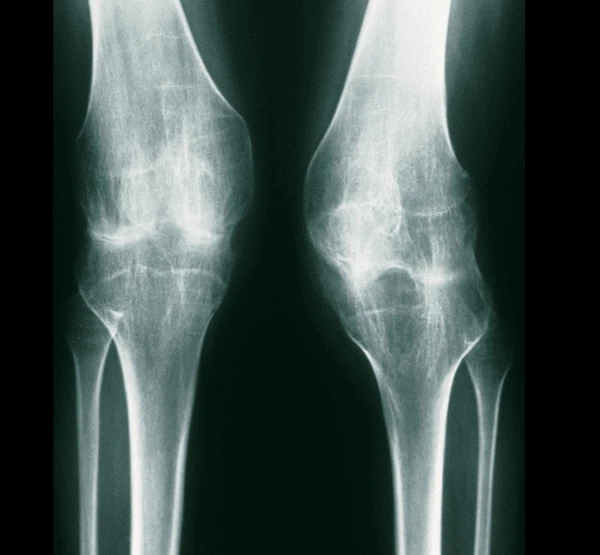

Hình ảnh học

X-quang hoặc cộng hưởng từ (MRI) có thể được dùng để loại trừ các bệnh lý khác. Chẳng hạn như gãy xương, u, nhiễm trùng hoặc dị tật bẩm sinh. Hình ảnh học cũng có thể được dùng nhiều lần sau chẩn đoán để đánh giá sự phát triển xương và phát hiện tổn thương khớp.